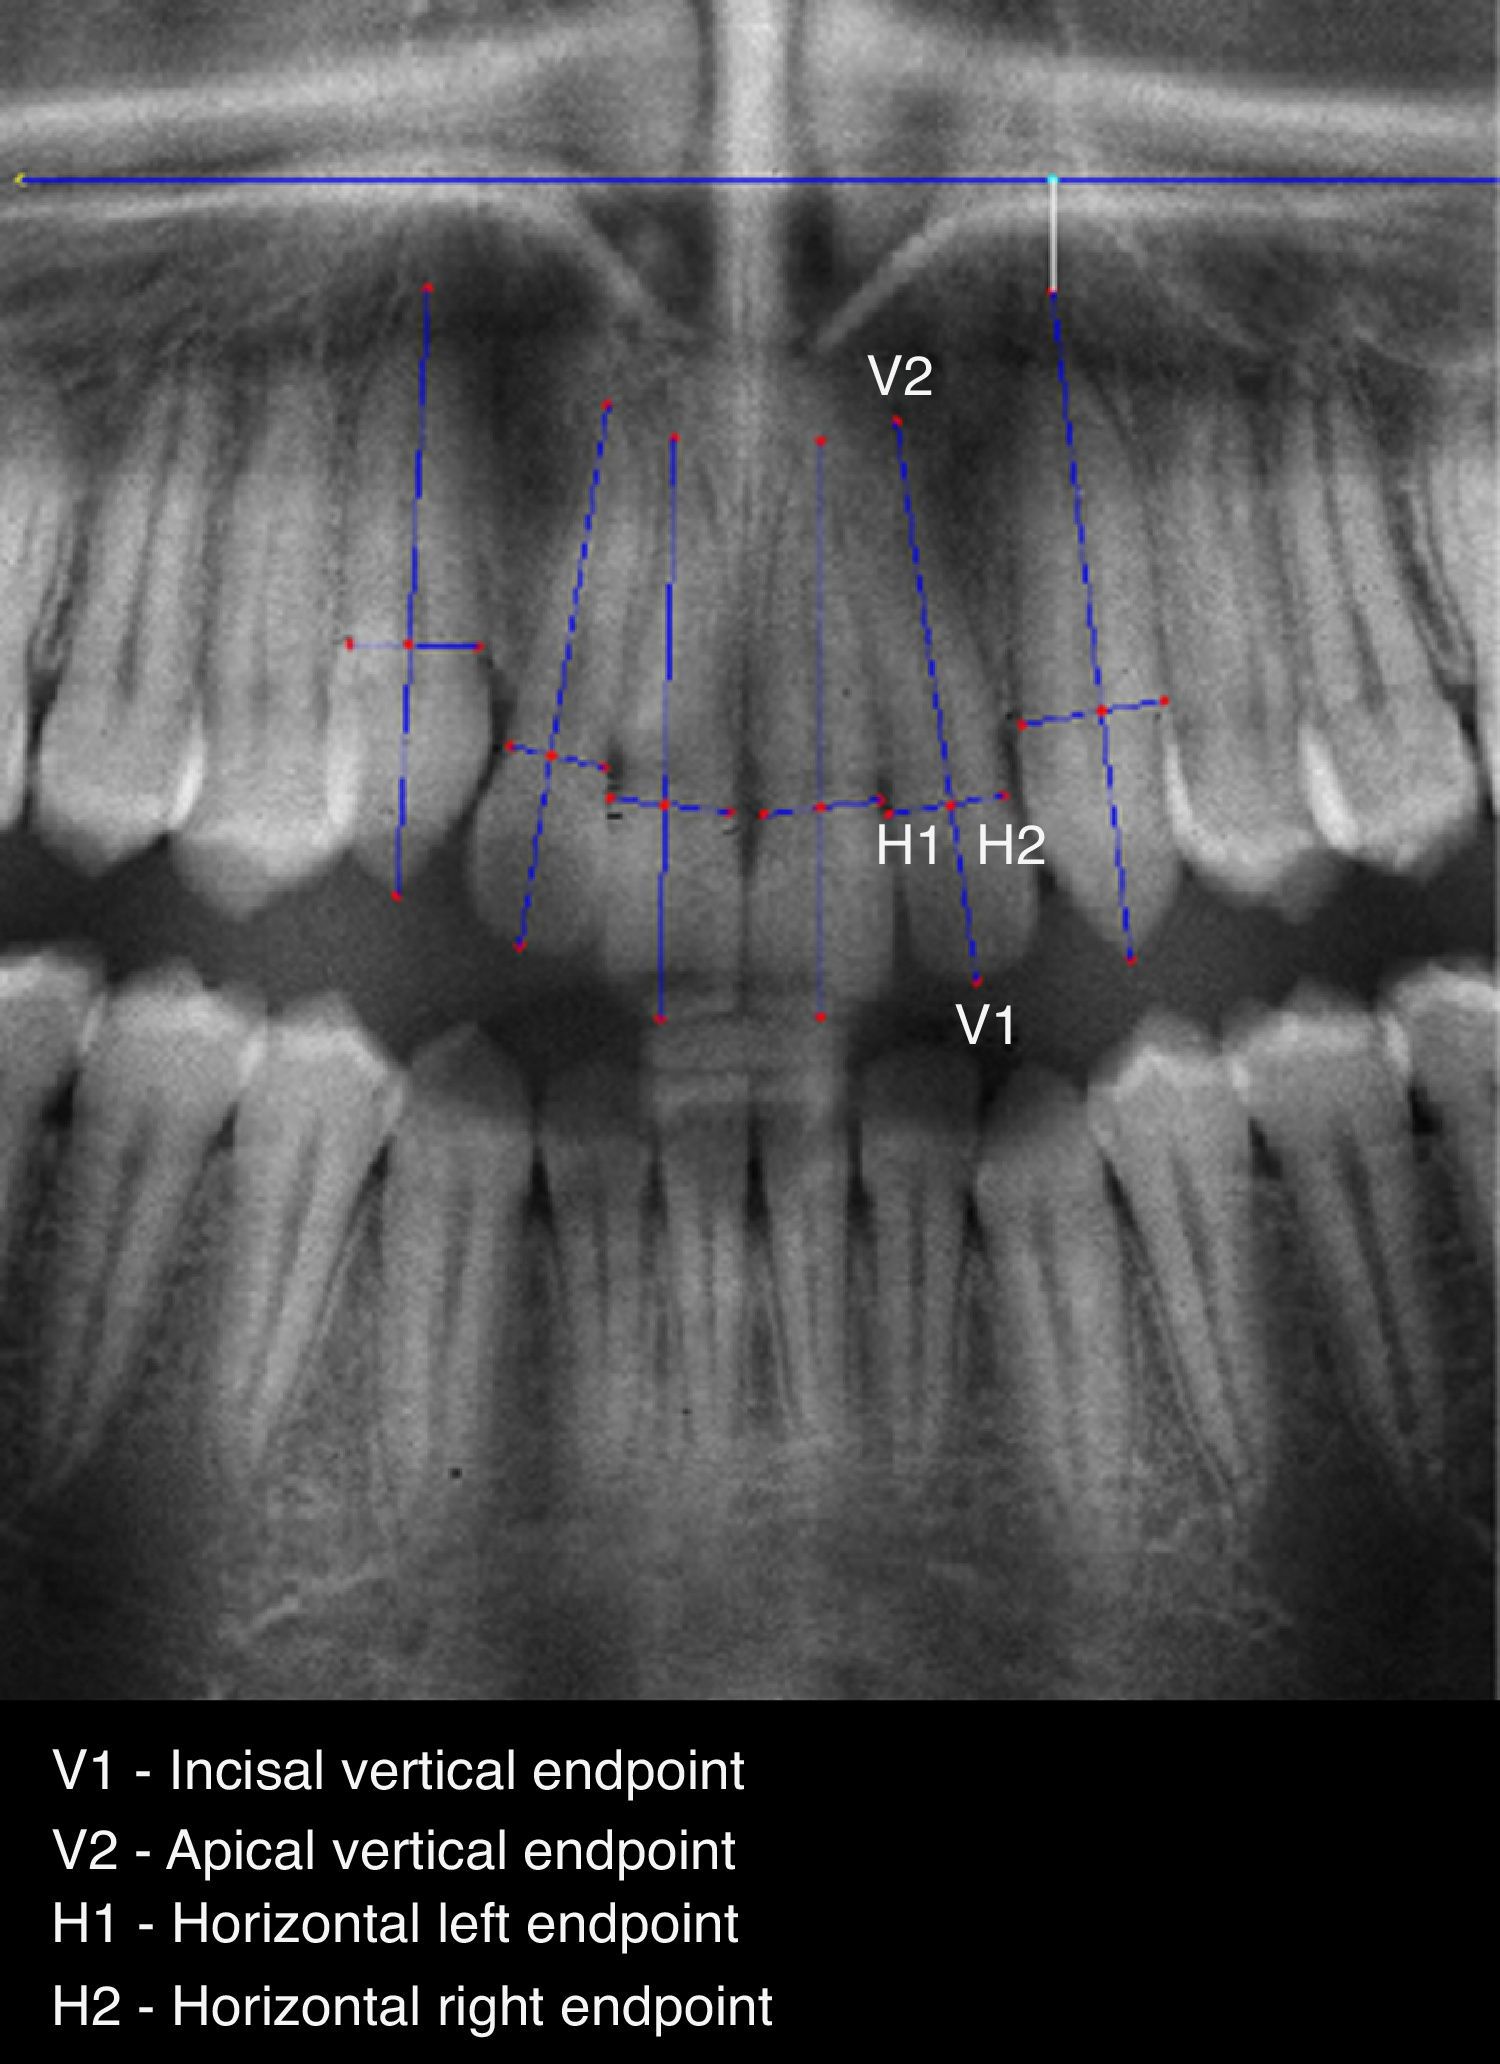

To allow a standardized and accurate method for measuring EARR, a software prototype (ARIAS – Apical Resorption Image Analysis System) in MATLAB version 7.12.0.635 (R2011a) was developed. The proposed method includes the following three steps: (1) image preprocessing, allowing the application of image enhancing filters; (2) point selection, manually marking 4 points on each selected tooth: two points, V1 and V2 (the vertical points) defining a vertical line segment outlining the intersection between root and crown, and two points H1 and H2 (the horizontal points) defining a horizontal line segment that represents the tooth width (Figs. 1 and 2) and (3) feature extraction, to automatically produce a set of linear measurements in T1 and T2 radiographic images, such as: initial root length (R1), initial crown length (C1), final root length (R2), final crown length (C2) and corrected final root length (CR2) – Table 1.

Data obtained from automatic computing of measurements,a using ARIAS.

| Teeth | T-1 Crown(C1) | T-1 Root(R1) | T-2 Crown(C2) | T-2 Root(R2) | Correction factor(CF) | Corrected R2(CR2) | %Remained root(CR2/R1) | %EARR |

| 13 | 55.04 | 88.09 | 56.14 | 88.20 | 0.98 | 86.47 | 0.98 | 2 |

| 12 | 42.76 | 87.86 | 42.95 | 67.47 | 1.00 | 67.16 | 0.76 | 24 |

| 11 | 46.01 | 88.05 | 47.38 | 61.66 | 0.97 | 59.88 | 0.68 | 32 |

| 21 | 47.00 | 87.00 | 46.10 | 68.12 | 1.02 | 69.45 | 0.80 | 20 |

| 22 | 41.44 | 87.82 | 43.01 | 65.01 | 0.96 | 62.63 | 0.71 | 29 |

| 23 | 59.41 | 98.62 | 60.41 | 92.54 | 0.98 | 91.02 | 0.92 | 8 |

It is accepted that during orthodontic treatment the crown length does not change, so, the ratio between the initial crown length and the final crown length (C1/C2) determines the enlargement factor to be used to determine the corrected final root. The six anterior maxillary teeth were measured using the Linge and Linge method,11 modified by Brezniak et al.23 The root and crown lengths in both T-1 and T-2 radiographic images were then used by the software to calculate the other parameters. Mathematical formulations computed to obtain the final %EARR are shown below: